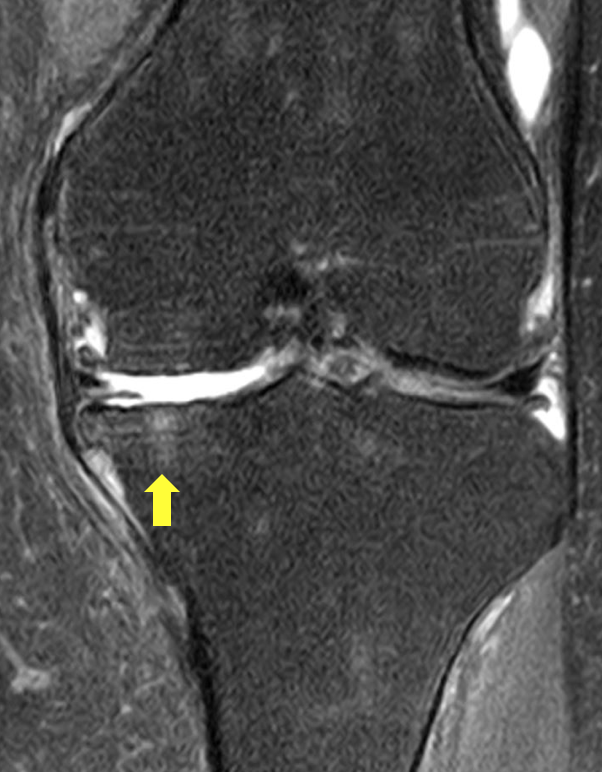

MRI撮影を行い、膝の脛骨にBMLを認めました。

そのため体外衝撃波治療を実施しました。

黄色矢印のところが白くなっています。

これがBMLです。

正面から見た画像とちょうど同じ部分に

BMLを認めています。